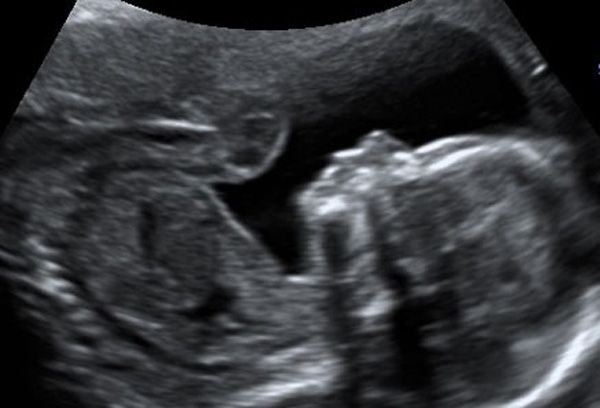

En gennemscanning af barnet fra uge 14+0

Ved valget af denne type scanning laves en gennemscanning af barnet, hvilket udføres i henhold til anvisninger fra DSOG (Dansk Selskab for Obstetrik og Gynækologi).

Under scanningen ser vi på flere af barnets organer, herunder bl.a. hjerte, nyrer og blære. Barnets hoved, mave og lårbensknogle måles og der ud fra laves en vækstberegning. Vi ser også på barnets arme, ben og føddernes rotation, rygsøjle og mellemgulv samt antal kar i navlesnoren. Vi kigger efter læbespalte og ser på begge øjenhuler og øjenæbler. Moderkagens placering ser vi også på og vi hører barnets hjerte. Ønsker I at kende barnets køn, kigger vi naturligvis også efter det.